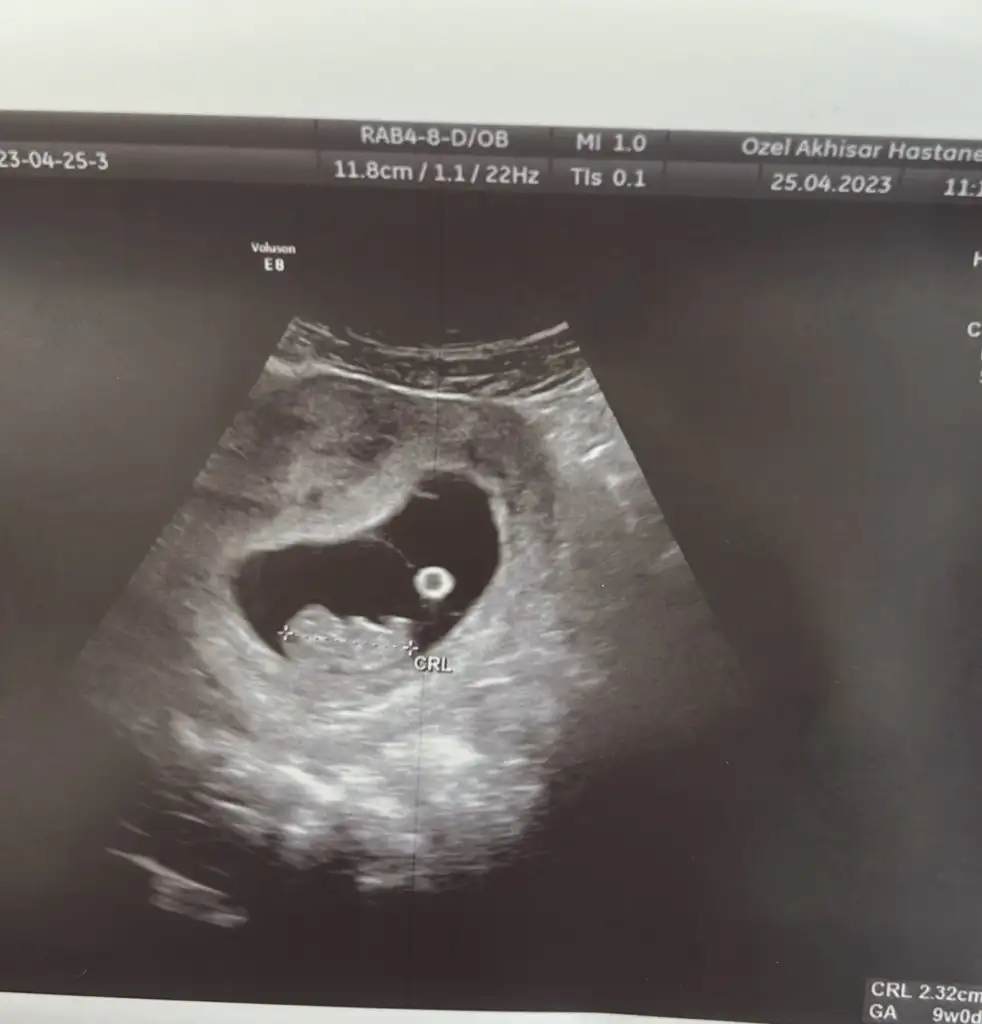

Merhabalar benim için de yorumda bulunmanızı rica edebilir miyim lütfen? Burada 9 haftalığız 🤗 şimdiden teşekkür ederim

• IMG-20230423-WA0006.webp

IMG-20230423-WA0006.webp

8,5 KB · Görüntüleme: 49